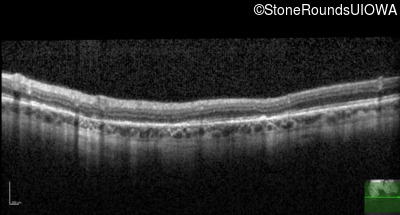

Optical Coherence Tomography - Right - 20/20 sc

Exemplar / OCT Stack